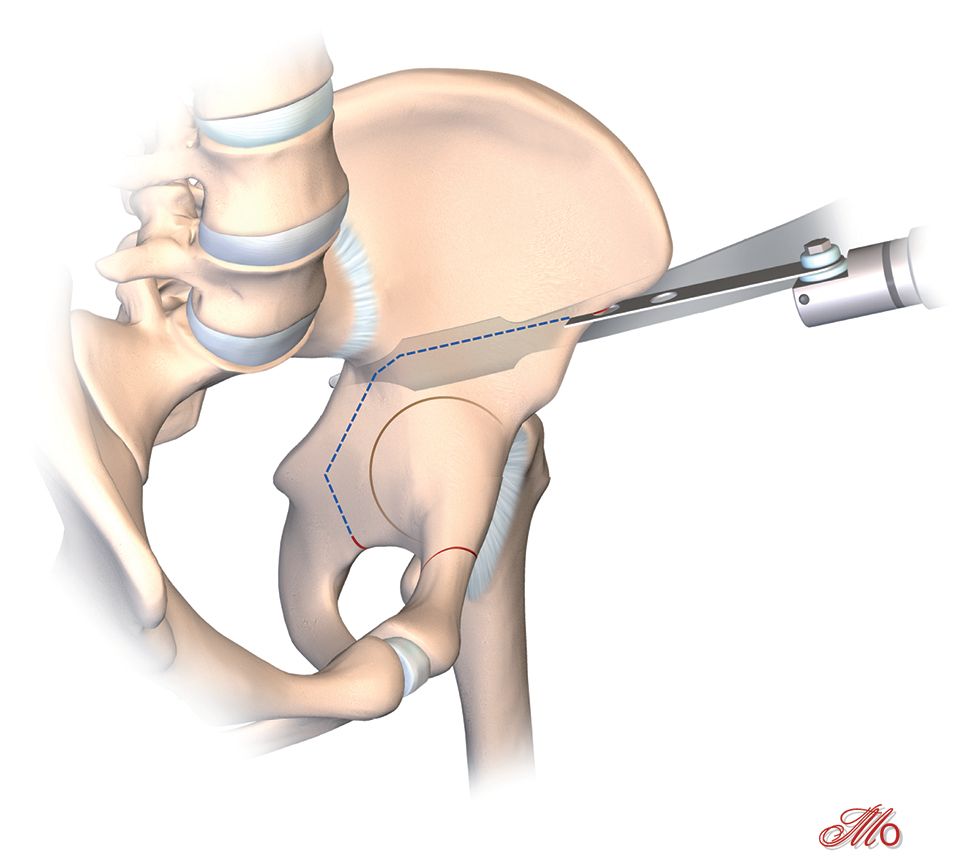

The patient is positioned supine on a radiolucent table to allow for intraoperative radiographs (Fig. 2). The first modification of the MIS PAO technique, versus conventional PAO is the bikini skin incision. The bikini skin incision (ilioinguinal) starts 2cm lateral from the anterior third of iliac crest to the anterior superior iliac spine (ASIS) and then follows the skin fold over the inguinal ligament toward the symphysis (Fig. 3).

The incomplete ischium osteotomy, preserving the posterior half of the posterior acetabular column, is performed under radiological control with a curved 15mm osteotome. The osteotomy is initiated at the infracotyloid groove, which can be palpated very clearly with the tip of the osteotome, and ascends toward the spina ischadica (Fig. 7). At this point of the operation the surgeon needs to be aware of the anatomical proximity of the sciatic nerve, avoid Intraarticular penetration with the osteotome and guard against transection of the posterior column (Fig. 7, 8). To reduce the risk of nerve injury, the hip is flexed and abducted for the osteotomy of the medial ischium (Fig. 9). For the osteotomy of the lateral ischium the leg is extended and externally rotated.

The retroacetabular osteotomy is performed at an angle of 110° relative to the supraacetabular osteotomy under fluoroscopic control (Fig. 14). Care must be taken to maintain a minimum bone stock of 1 cm prior to the sciatic notch to ensure the integrity of the posterior half of the posterior acetabular column. This ensures the continuity of the posterior column and provides the pelvic stability needed for postoperative mobilization and weight bearing.

After these osteotomies the acetabular fragment should be careful mobilized with a laminar spreader and 1 Steinmann-pin (Fig. 15). Often there are still same bone brides between the ischium and the retroacetabular osteotomies. These bridges should be brocken with a curved osteotome which is placed under fluoroscopic control and after spreading the osteotomy with a laminar spreader. After all osteotomies are finished, acetabular reorientation remains a difficult step and care should be taken to achieve proper acetabular reorientation. The goal of reorientation is an LCE of 30°, a positive acetabular index and an anteverted acetabulum The reoriented acetabulum is then temporarily secured by two Kirschner wires that bridge the supraacetabular osteotomy (Fig. 15).